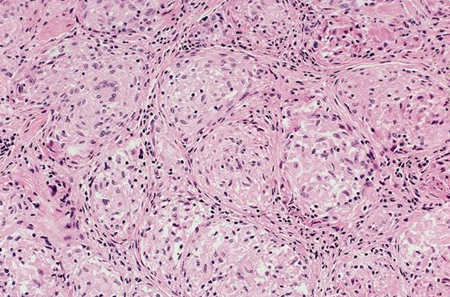

Photomicrograph showing well-formed granulomas typical for sarcoidosis

From the collection of Dr M.P. Muthiah; used with permission